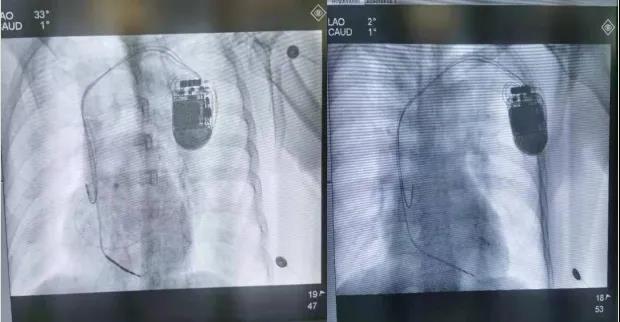

呼和浩特市第一医院心血管内科病例分享——CRT-D手术

2021年11月22日,呼和浩特市第一医院心血管内科团队在侯煜院长及高江峰主任的带领下,再次为一名64岁患者成功植入CRT-D,此次手术在既往的基础上进一步改进和优化,彰显我院对顽固性心衰及恶性心律失常的治疗水平进一步提升。

患者,男,64岁,10年前因急性心肌梗死在外院行急诊PCI植入支架一枚,2021年7月出现胸憋、心悸,伴肩背部疼痛及咽喉部紧缩感,就诊于我院行心电图检查示室性心动过速,给予抗心律失常药物无效,电复律后恢复窦性心律。2021年11月11日再发室性心动过速于我院急诊科电复律转窦后转入我科。室性心动过速是心肌梗死后常见的恶性心律失常,极易发展成室扑、室颤,可危及生命,是心源性猝死的主要原因。鉴于患者反复出现恶性心律失常,猝死风险高,入院后科室高度重视,开展疑难危重病历讨论,并向侯煜院长及高江峰主任汇报患者病情。患者反复多次出现室性心动过速,且心彩超提示心脏扩大,左室射血分数明显降低,BNP明显升高,患者已出现明显心力衰竭表现,药物治疗效果差,心电图QRS波明显增宽,猝死风险极高,经过与患者及家属的多次沟通,经过综合分析及充分论证,决定为患者安装CRT-D,手术历时1小时40分钟,圆满成功。在既往CRT-D手术基础上,进一步改进和优化。本次手术使用先进的DF4除颤导线和Quartet左室四极导线,DF4除颤导线配合三合一除颤端口,将传统CRT-D的8颗螺丝减至3颗,缩短了手术时间,有效减小囊袋体积,降低感染风险,左室四极导线,可从10个向量测试左室起博阈值,增强恶性心律失常的识别,提升了CRT-D除颤及起博功能的有效性及安全性,有效降低患者猝死的风险。术后患者心电图QRS波宽度明显缩小,患者心衰症状明显改善,仅在患者胸部留有一处小切口,切口愈合良好,未出现切口感染。患者及家属对手术非常满意。